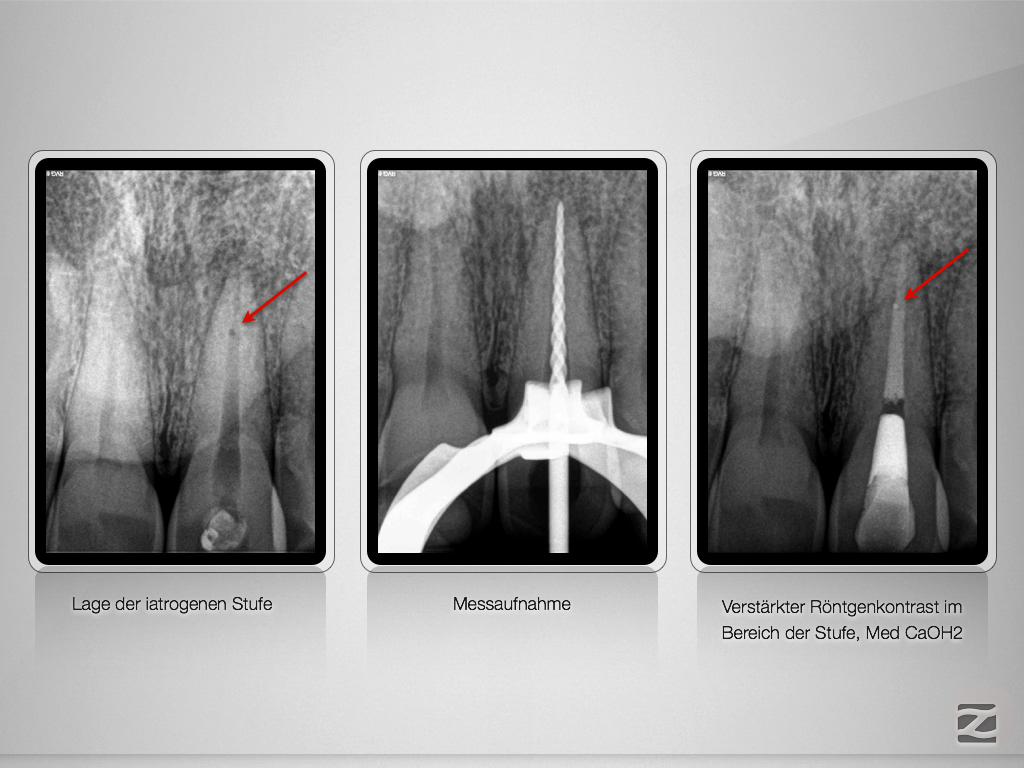

21D.003

Tücke des Details